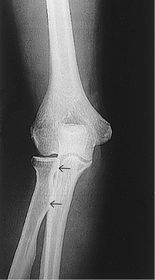

A. humerus B. coronoid fossa C. medial epicondyle D. humeral condyle E. trochlea F. trochlear sulcus G. radial head H. capitulum I. lateral epicondyle J. radial fossa

A. medial epicondyle B. trochlea C. coronoid tubercle D. radial head E. capitulum F. lateral epicondyle H. olecranon process

AP Elbow Fully Extended 60-75 kV 40 SID 14x17 IR nongrid CR @ mid-elbow joint MUST SEE entire elbow joint very slight superimposition of radial head by the ulna